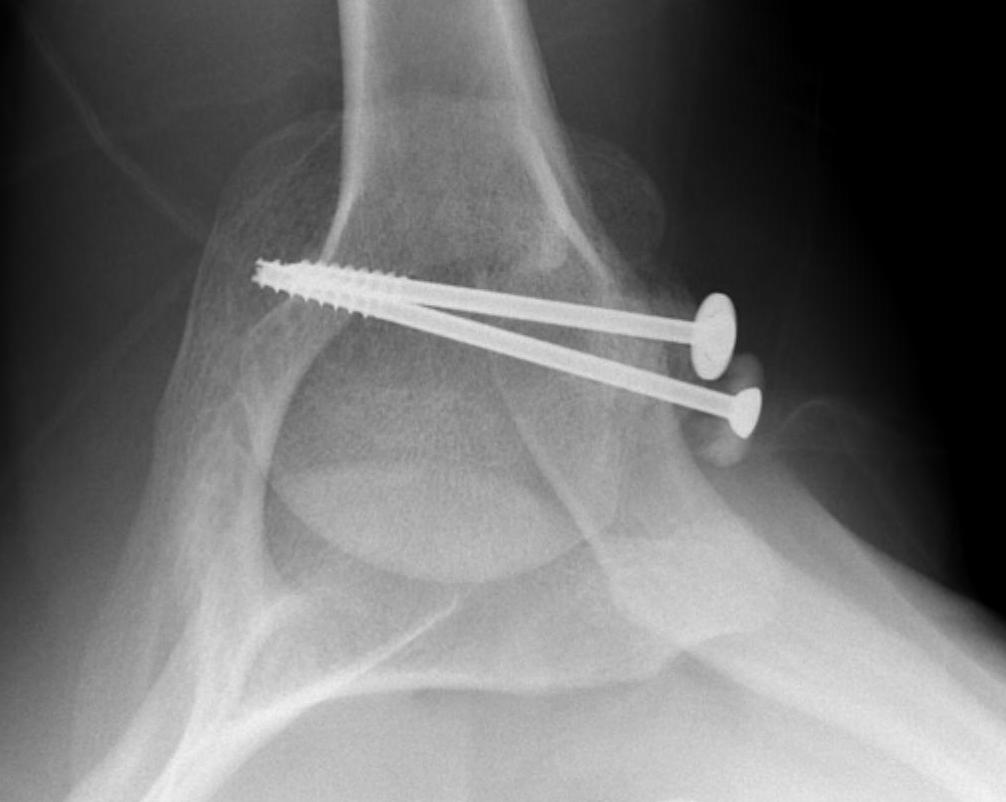

proximal humerus fracture Background ORIF with locking plate Arthroplasty Greater tuberosity fractures Lesser tuberosity fractures / avulsions Book traversal links for Proximal humerus fractures ‹ Pectoralis Major Tears Up Background ›